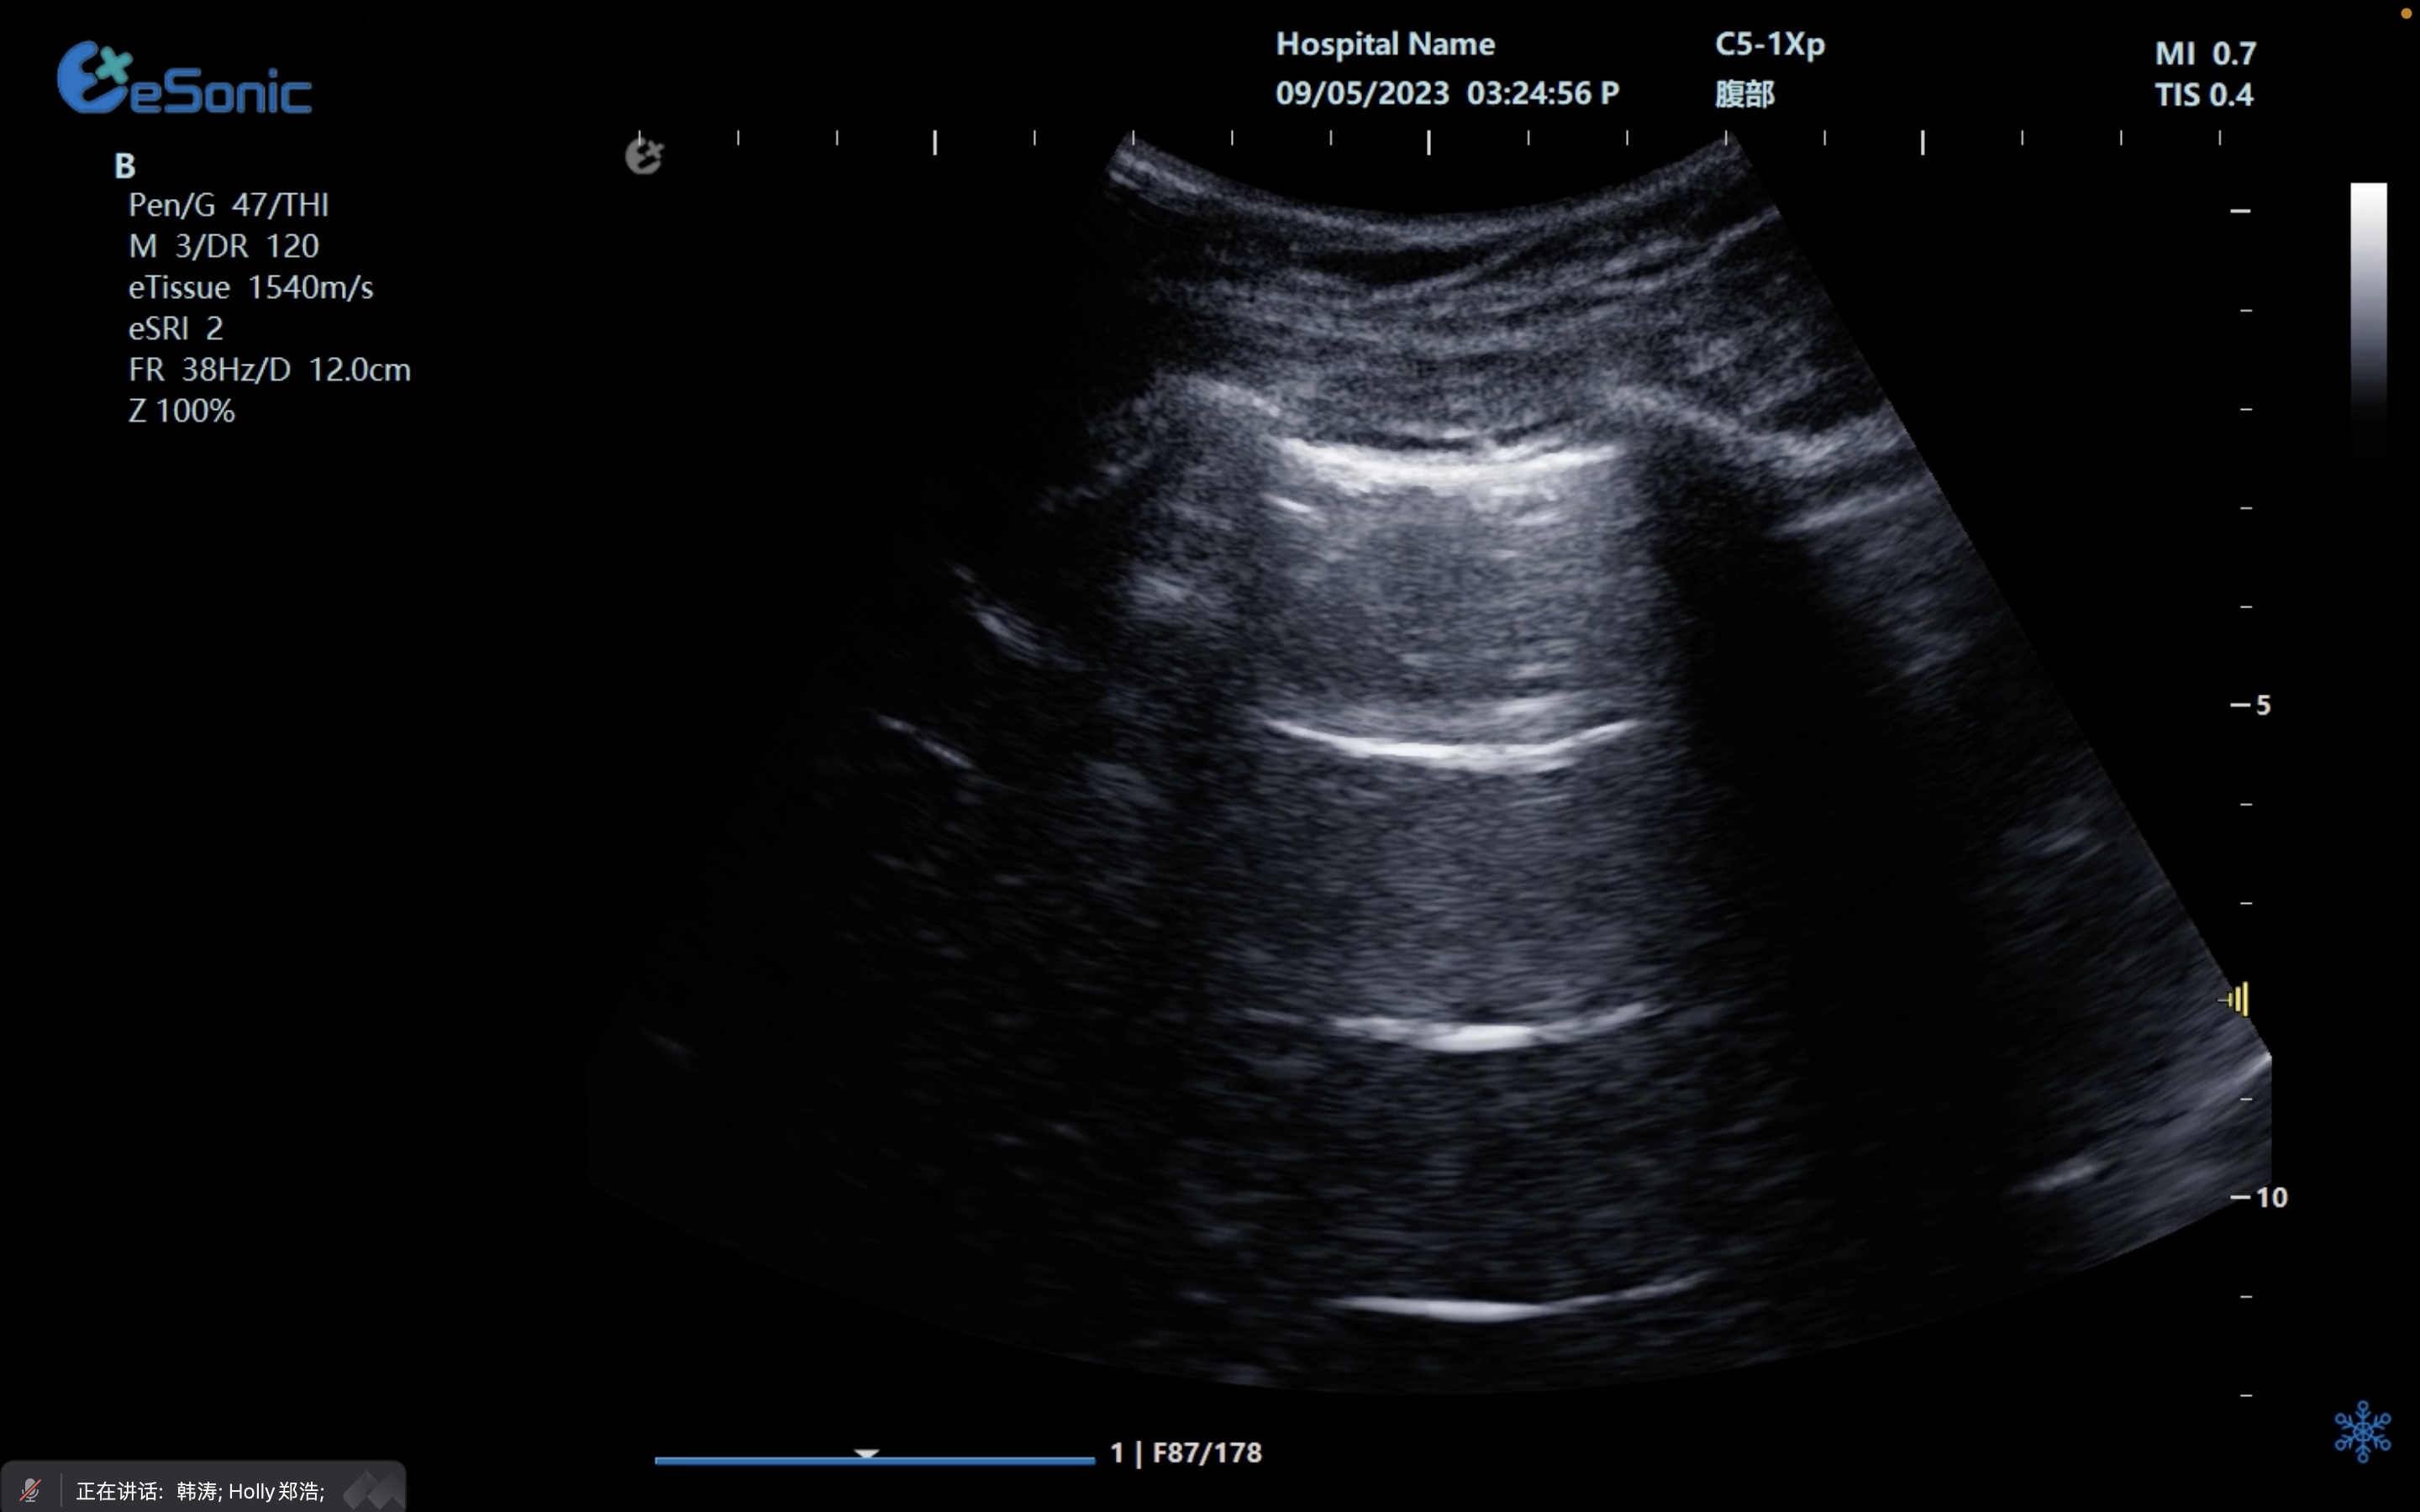

剑突下下腔静脉切面

扫查方法:在剑突下四腔心切面的基础上逆时针调整探头,直至标记指向被检者的头部,轻轻将探头向被检者右边倾斜。

超声声像图:显示右房,下腔静脉及肝静脉,注意观察下腔静脉及肝静脉有无扩张及搏动。

创伤评估FAST

image.png